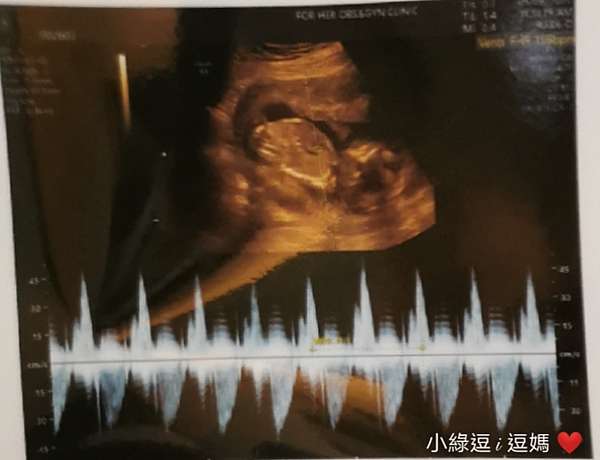

二寶日記 12w 4 開獎日 男孩女孩一樣好兩胎初期症狀比較 小綠逗i逗媽 痞客邦